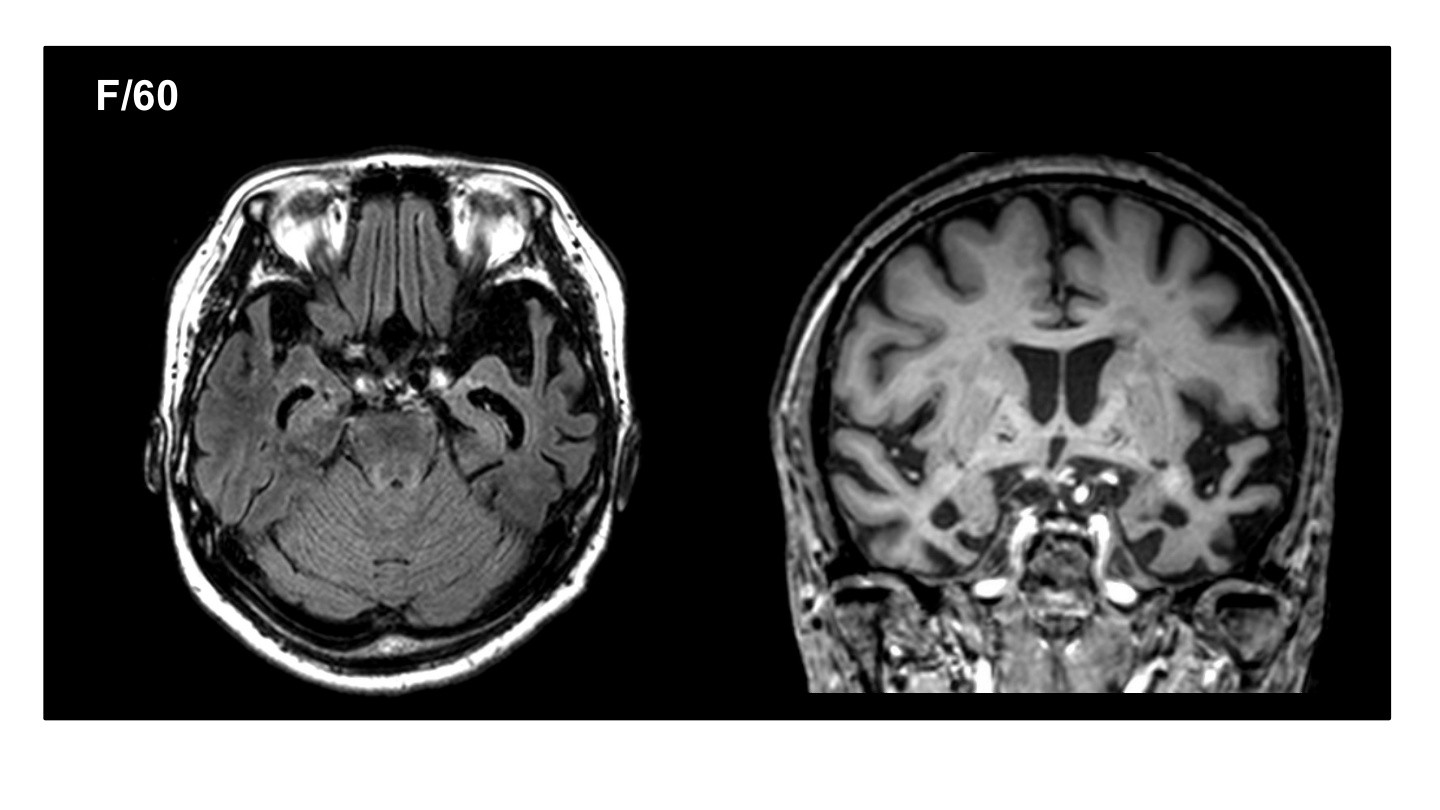

현재 삼성서울병원 신경과 교수로 재직 중이신 김준표 교수님은 신경과 레지던트, 전임의, 임상조교수로 활동하시며 대한치매학회 위원으로서 치매와 신경과학 분야에서 깊은 전문성과 풍부한 경력을 쌓아오셨습니다. 특히, SCI급 논문 55편을 게재하며 학문적 연구에도 크게 기여하셨습니다. 이번 강연에서는 치매의 진단, 치료, 예방에 대한 귀중한 통찰을 나눠주실 예정입니다.

현대사회에서 치매는 우리 주변에서 점점 더 빈번하게 접할 수 있는 중요한 건강 문제로 떠오르고 있습니다. 이번 강의를 통해 치매를 진단하고, 효과적으로 치료하며, 예방할 수 있는 실질적인 방안에 대해 알아볼 수 있는 소중한 시간을 가질 수 있을 것 같습니다. 치매 분야에서 오랜 경험을 지닌 교수님의 강의를 통해 치매에 대한 더 깊은 이해와 대비책을 마련할 기회를 함께 가져보시길 바랍니다.